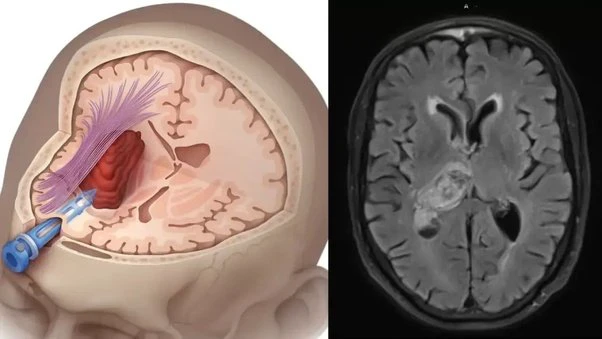

Brain Stroke Alert। ब्रेन स्ट्रोक एक ऐसी खतरनाक और अचानक होने वाली मेडिकल कंडीशन है जिसमें दिमाग की किसी नस के ब्लॉक या फट जाने से मस्तिष्क को ऑक्सीजन मिलना बंद हो जाता है। इसका सही समय पर इलाज न मिले तो जान भी जा सकती है। लेकिन इससे पहले शरीर आपको एक खामोश चेतावनी देता है—मिनी ब्रेन स्ट्रोक, जिसे मेडिकल भाषा में ट्रांसिएंट इस्केमिक अटैक (TIA) भी कहते हैं।यह बड़ा अटैक आने का 24 घंटे पहले का संकेत हो सकता है। इसे पहचान लेना जिंदगी बचा सकता है।

NHS के मुताबिक, जब दिमाग की किसी नस में कुछ देर के लिए ब्लॉकेज होता है, तो मस्तिष्क तक ऑक्सीजन का प्रवाह रुक जाता है। यह स्थिति कुछ मिनटों से लेकर 24 घंटे तक रह सकती है।

अच्छी बात यह है कि यह स्थायी नुकसान नहीं पहुंचाता, लेकिन इसे नज़रअंदाज़ करना बेहद खतरनाक हो सकता है—क्योंकि इसके बाद बड़ा ब्रेन स्ट्रोक आने का खतरा कई गुना बढ़ जाता है।